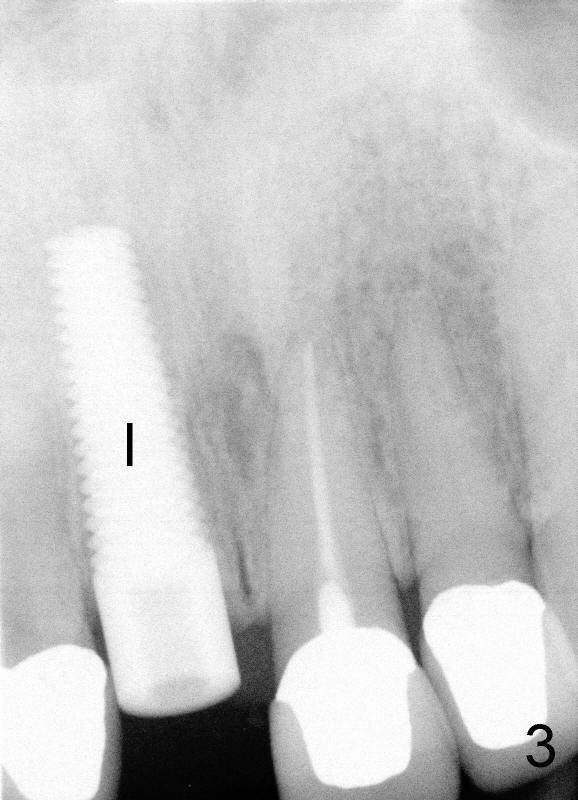

A 44-year-old lady has fractured #8 and agrees to have the tooth extracted after failure of recementation (Fig.1).  Pre-implantation X-ray shows minimal periapical radiolucency (Fig.2: >).  A 5x20 Tatum tapered implant is placed immediately after extraction (Fig.3: I).  Perio dressing is placed and a flipper is delivered.

Sixteen days after surgery, the patient returned with chief complaint "I do not have pain, but there is a swelling".  Exam shows that there is localized apical swelling with + fluctuance (Fig.4: *) and granulation tissue at gingival margin (>).  Under local anesthesia, I & D is performed with sanguine exudate, buccal apical plate perforation with implant threads exposed.  Tetracycline normal saline is used for irrigation.  The patient was asked to return every 1-2 days for irrigation.